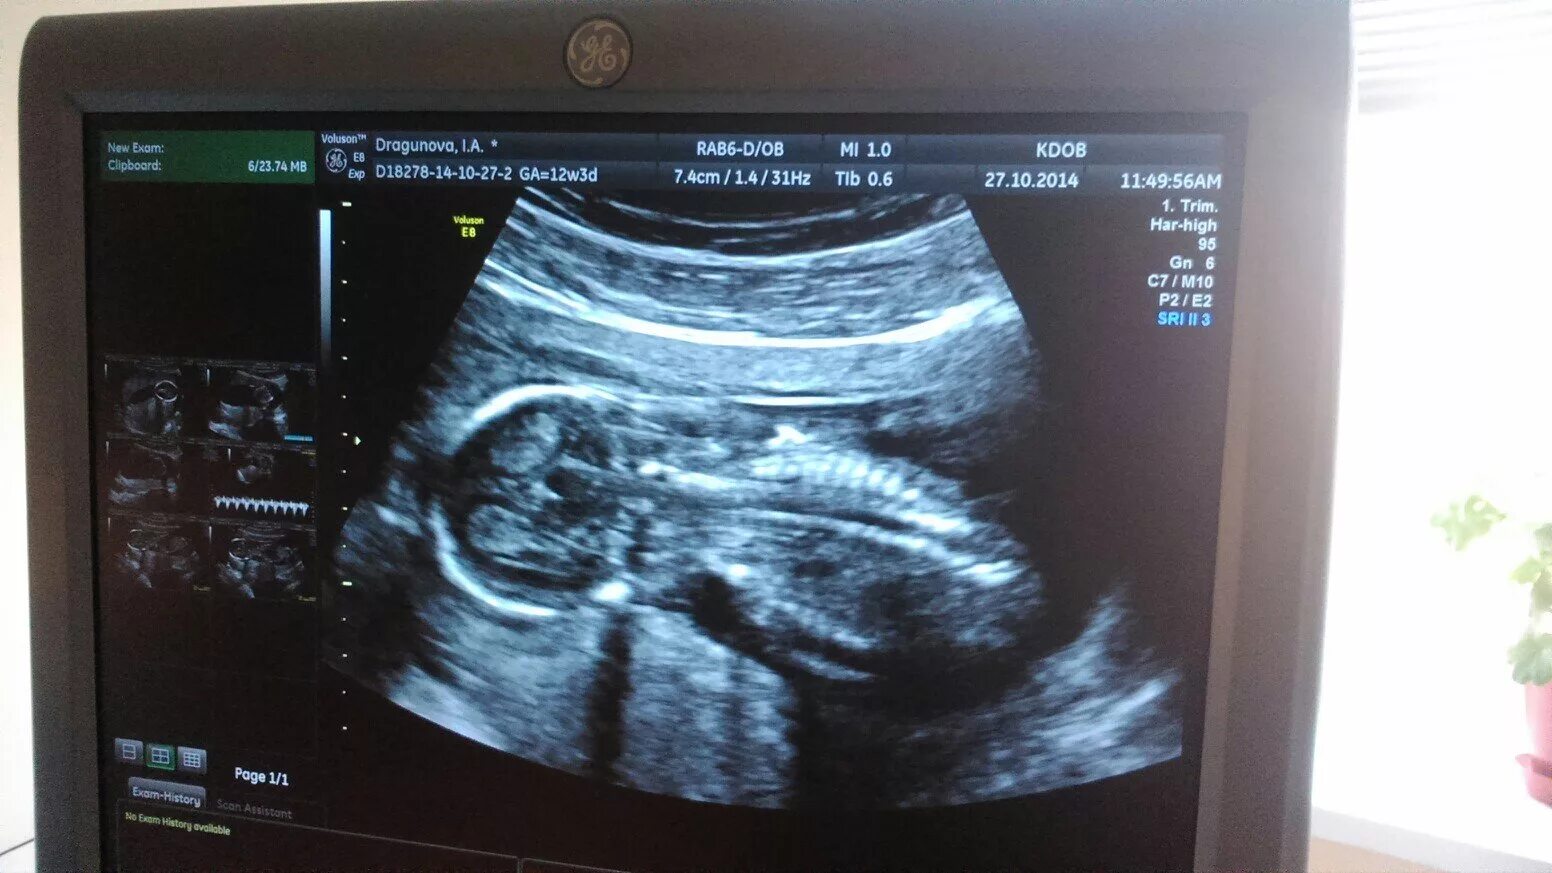

Скрининг 10